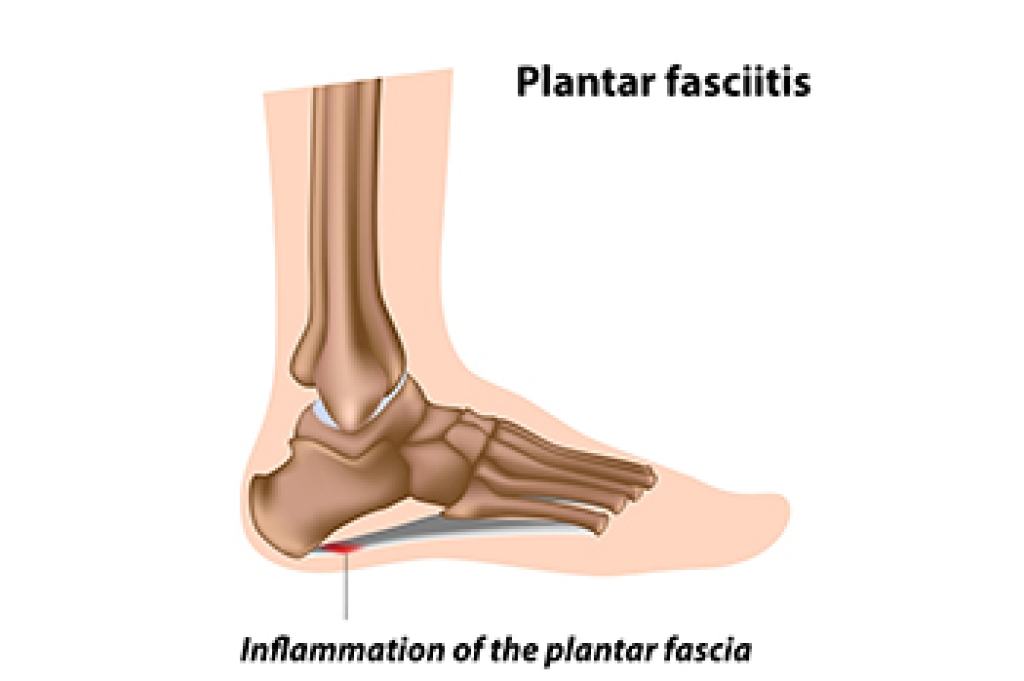

- Plantar fasciitis